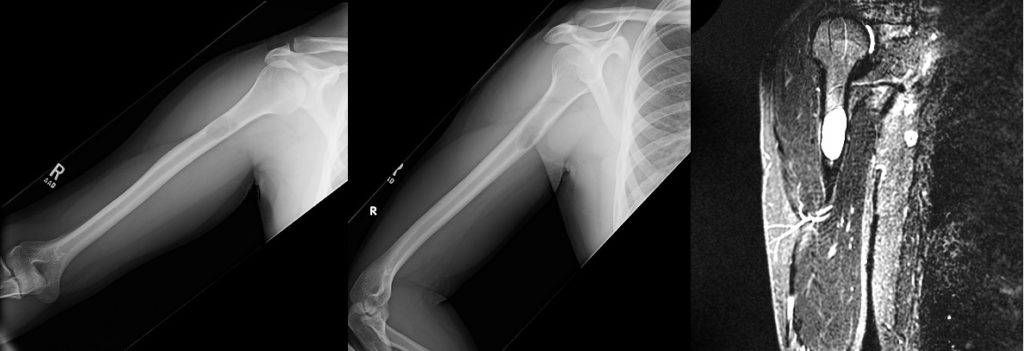

A 79-year old female presents with complaints of right hip pain for 2 months. She denies prior injury or precipitating event. The pain is made worse by lying on the affected side and occasionally hurts with hip motion. The pain is improved with NSAIDS and placing ice on the lateral aspect of her hip. Her primary care physician ordered x-rays which showed a bone lesion in the proximal femur. Her PCP was concerned she had bone cancer and ordered an MRI of the thigh to further evaluate. AP x-ray and a coronal MRI image are shown above. The patient denies a history of weight loss, fatigue, and history of cancer. On exam the patient has no pain with passive range of motion of the hip in all planes. She has pain with palpation over the greater trochanteric bursae. Motor and sensation are intact throughout the lower extremities. What is the most likely cause of this patient’s pain?